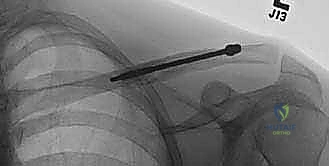

في تقنية التثبيت داخل النخاع، يتم استغلال هذه القناة الطبيعية لتمرير المسمار أو القضيب المرن بداخلها، مما يجعل المسمار يعمل كدعامة داخلية (Internal Splint) تتحمل الأحمال وتشاركها مع العظم (Load-sharing)، بدلاً من تحملها بالكامل كما تفعل الشرائح المعدنية الخارجية (Load-bearing).

هذه هي التقنية المتقدمة التي يتميز بها البروفيسور محمد هطيف. بدلاً من وضع شريحة خارجية، يتم إدخال مسمار أو قضيب مرن (مثل مسمار التيتانيوم المرن TEN أو مسامير مصممة خصيصًا للترقوة) داخل تجويف العظم (القناة النخاعية).